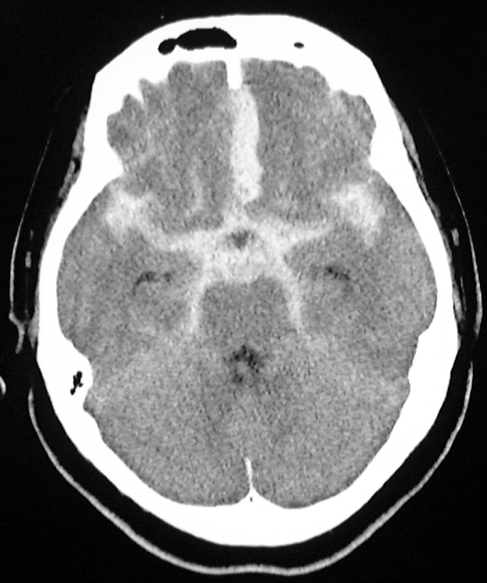

<頭部CT >

くも膜下出血の診断にはCTによるクモ膜下腔の高吸収の検出が適しており、発症24時間以内の診断率は92%で、以降時間の経過とともに低下します。すなわち、発症して救急車ですぐに病院に来られた場合には、診断率がよいということになりますが、2−3日経ってから(幸い再破裂などなく)、来院された場合には診断率が低下いたしますので、場合によってはCTのみでは診断ができない、誤診するということもありえるのです。

<典型的なくも膜下出血のCT画像>